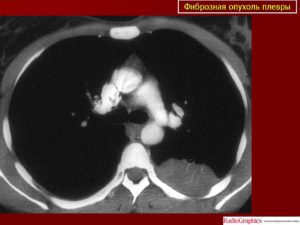

Компьютерную томографию легких (МРТ, ПЭТ) применяют для уточнения локализации и распространенности рака плевры, обнаружения инфильтрации грудной клетки, поражения легкого, медиастинальных лимфоузлов, перикарда, противоположного легкого.

- Компьютерная томография дает хорошую картинку, на которой прекрасно видна опухоль, ее размер и форма. Также можно оценить состояние соседних органов и тканей.

Компьютерная томография назначается для более детальной оценки мезотелиомы. С помощью КТ уточняется степень распространенности рака. Эту процедуру дополняет МРТ, посредством которого удается выявить наличие метастаз в соседние ткани и органы.